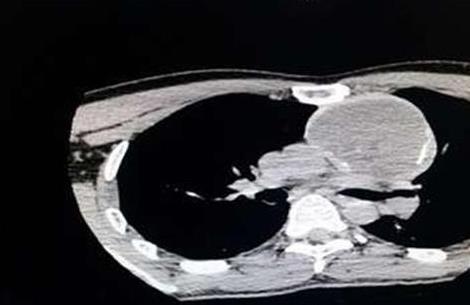

45岁徐先生近日莫名肩痛,一检查竟是左侧胸腔寄生了一个柚子大的畸胎瘤在作怪,瘤体已经将徐先生左侧锁骨下的血管“吞噬”8厘米,最可怕的是血管内的血栓随时都可能脱落而危及生命。昨(4)日,徐先生在新桥医院胸外科成功接受手术后康复出院。

家住荣昌的徐先生介绍,春节前,正在外地打工觉得自己肩部有点痛,以为是劳损引起的,就去做了按摩,贴了膏药,疼痛有所缓解,但几天后又疼起来。他到新桥医院做了CT才知道,左侧胸腔有8×7cm大小的畸胎瘤。医生告诉他,这个畸胎瘤可能自他生下来就有,此后逐渐长大。

“畸胎瘤将左侧锁骨下下静脉、无名静脉“吞噬”了8厘米长,并且导致血流变慢,形成了血栓,血栓随时都可能脱落而致肺部栓塞、心衰等而危及生命。”新桥医院胸外科余祖滨副教授介绍,如果不手术,畸胎瘤将逐渐增大,进而“吞噬”主动脉、心脏等,那时就没法手术,所以尽快手术切除畸胎瘤。